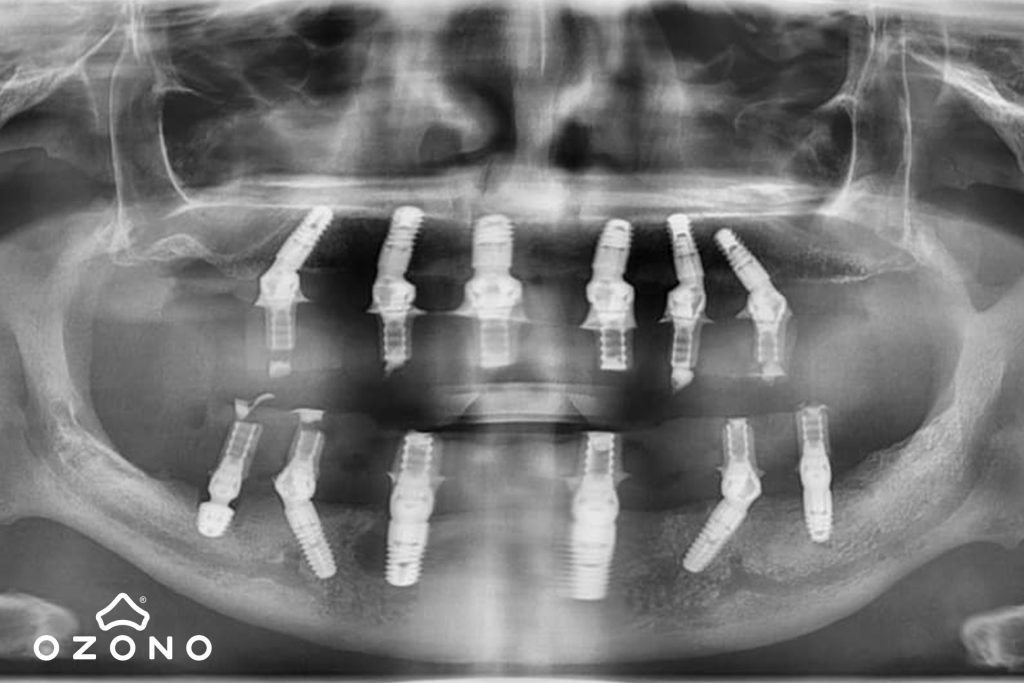

Pacientul implicat în acest proiect, cu grave probleme medicale stomatologice, nu ar fi avut nicio posibilitate să beneficieze de tratament implantologic, fără ajutorul nostru. Cazul său, preluat de Dr. Raluca Tureac, medic protetician în cadrul grupului CardioDent-OZONO, a fost analizat de către echipa multidisciplinară și s-a ajuns la concluzia că singura variantă de tratament este Sky Fast&Fixed de la Bredent, Germania, adică dinți ficși în 24 de ore, atât mandibular cât și maxilar, deoarece varianta de protezare mobilă nu a putut fi acceptată de către pacientul nostru, care se confrunta cu un reflex de vomă exagerat.

După partea teoretică, din blocul operator OZONO s-a făcut transmisia live a intervenției de implantare bimaxilară a pacientului preluat de Dr. Raluca Tureac, în vârstă de 63 ani. Acesta se confrunta cu o serie de probleme stomatologice complexe, din cauza cărora masticația nu mai putea fi realizată corespunzător, iar viața sa psihosocială era afectată.

Pe tot parcursul intervenției participanții au vizualizat în detaliu manoperele (extracția dinților restanți de pe ambele arcade și inserarea a 6 implanturi la maxilar și 6 implanturi la mandibulă), cu explicații pentru fiecare pas și situație clinică întâlnită. Dupa încheierea intervenției, pacientului i s-au înregistrat și amprentele necesare protezării din ziua următoare.